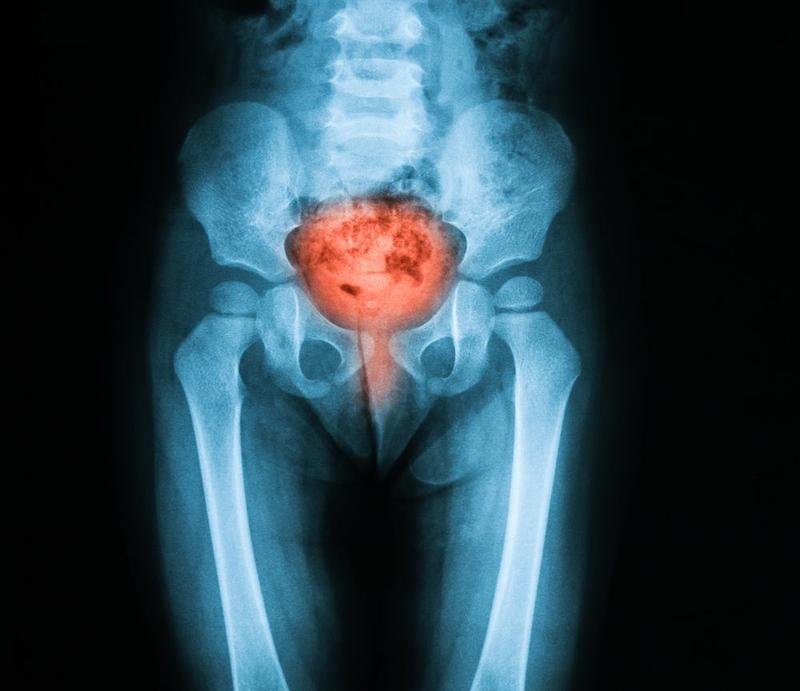

Leczenie farmakologiczne to bardzo szeroki temat. Szczególnie istotne są preparaty na infekcje dróg moczowych, na przykład zapalenie pęcherza. Wiadomo, bakterie nie znają granic. Ich ulubioną trasą do pęcherza jest cewka moczowa. U kobiet ta droga jest krótsza. Dlatego wiele kobiet doświadczy tego uciążliwego problemu w swoim życiu. Tu wkracza arsenał farmakologiczny! Od ziół po tabletki – mamy w czym wybierać.